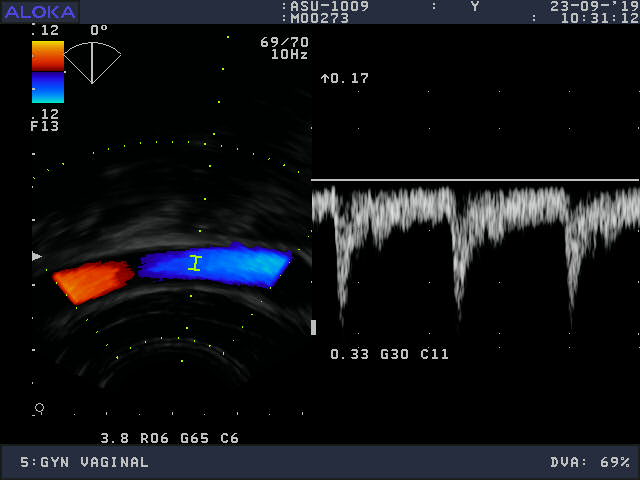

Volume Obstetric and Gynecology

Frequency Range: 9 – 3 MHz

Aloka ASU-1003 3D/4D Vaginal – ProSound for Volume Obstetric and Gynecology

| Type of examination 3D/4D | |